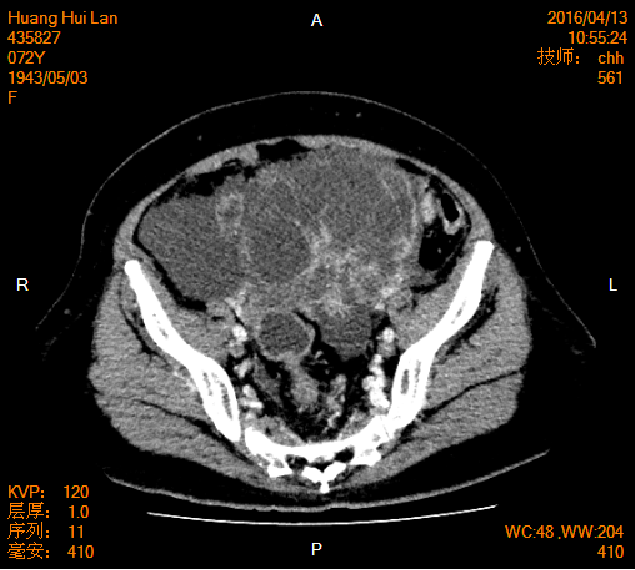

2016-04-13胸腹盆CT

左侧附件区肿块,代谢活跃,考虑卵巢囊腺癌;直肠壁增厚,代谢活跃,考虑直肠癌并周围淋巴结转移可能性大,建议肠镜检查;双肺多发结节,考虑转移瘤;腹腔积液